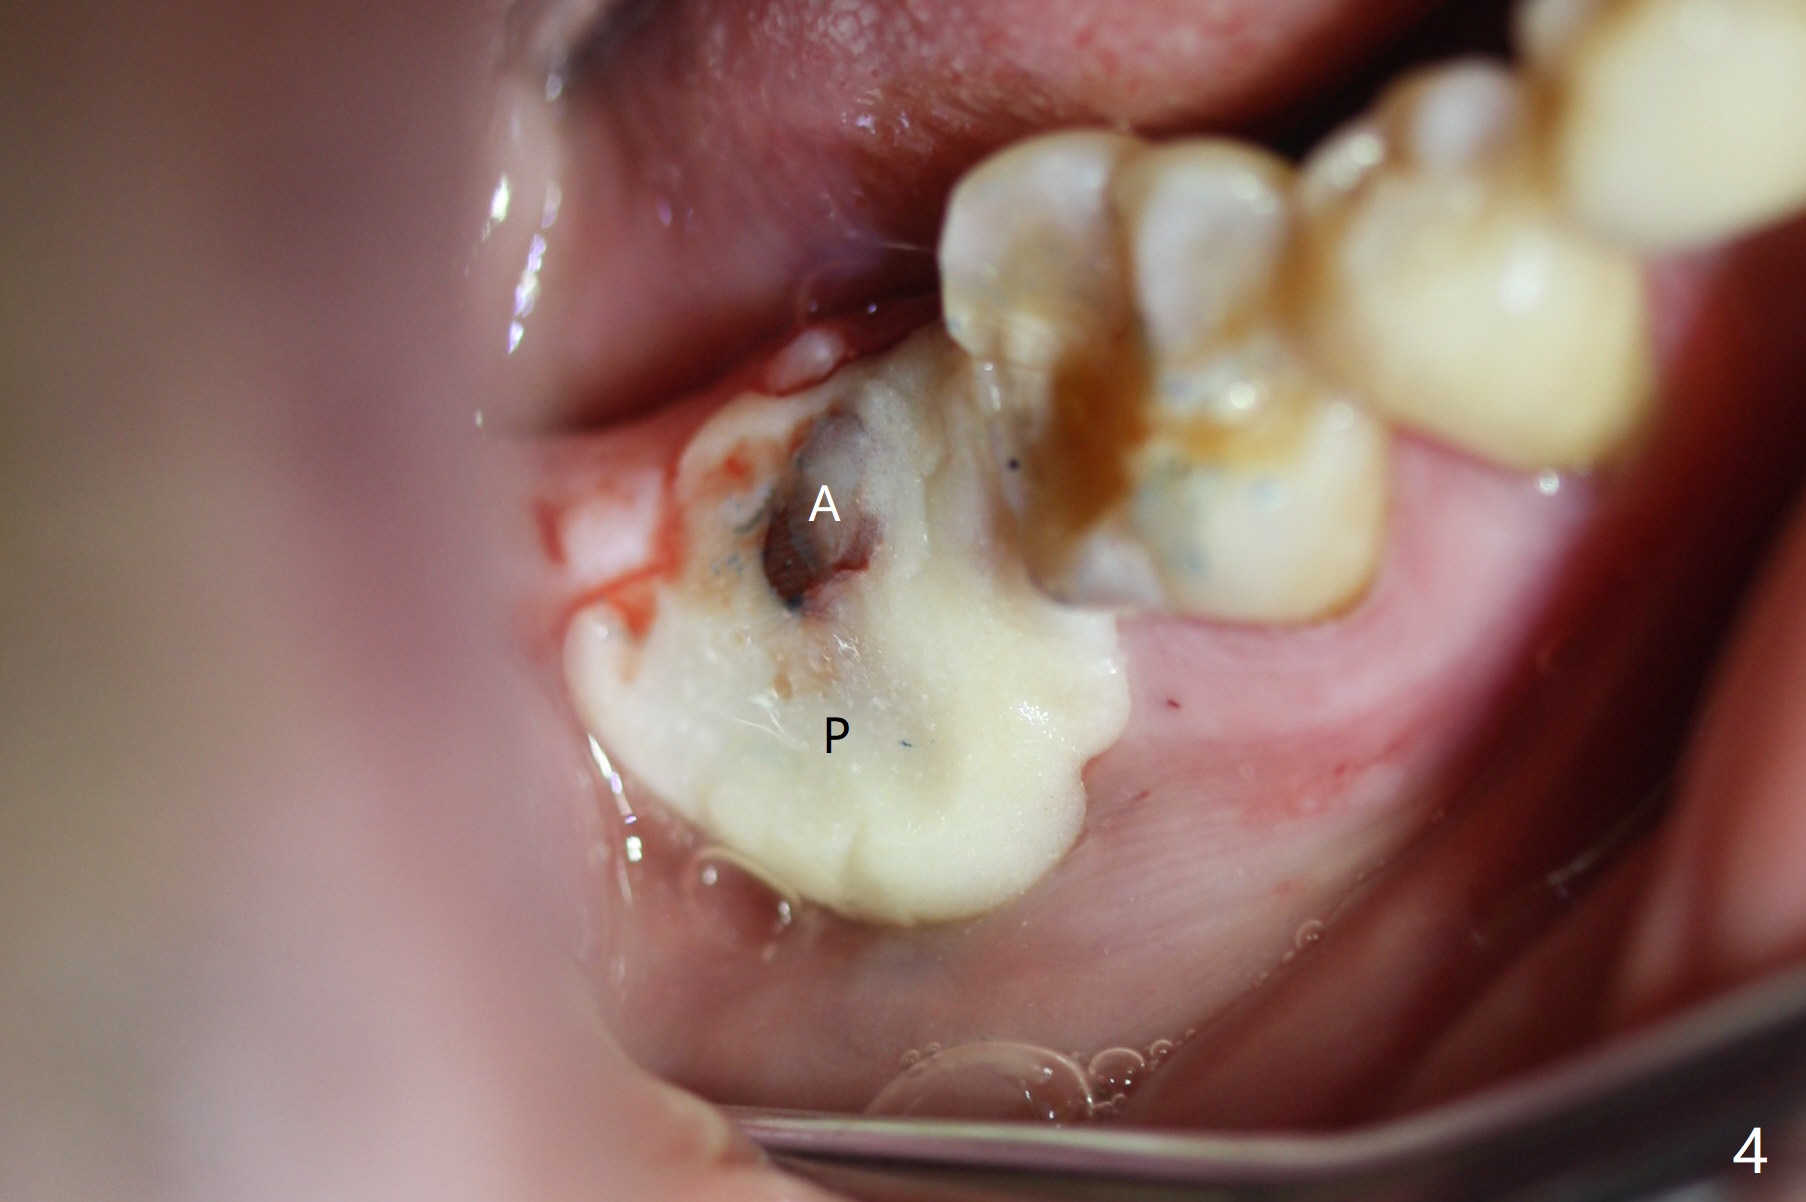

The residual roots of the tooth #31 are lower buccal (Fig.1 B), which in fact is molded and worn by the supraerupted tooth #2. When the tooth is extracted (Fig.2) and an implant, abutment (Fig.3 gold colored) and allograft (*) are placed, the abutment has to be trimmed. An atypical immediate provisional is fabricated by spreading setting acrylic over the abutment and bone graft (Fig.4 P) with occlusal equilibrium. Advantages of the guided surgery are good position (Fig.3 buccolingual), trajectory and depth (Fig.5,6) of the implant. The buccodistally exposed implant threads are packed with allograft in sufficient amount (Fig.3,5,6 *). The atypical immediate provisional breaks down and dislodges 3 weeks postop (Fig.7). In fact the implant plateau is exposed buccally. A monojet is given to the patient for self cleansing. He is instructed to return in 3 weeks. The exposed implant threads are covered 1.5 months postop (Fig.8). Incomplete abutment seating (Fig.9 <) was not noted until 1 year 3 month post cementation when the crown was mobile (Fig.10). A 6x3 mm healing abutment is placed. Three days later, the crown is sectioned and separated from the abutment. The latter returns to place; due to angulation associated with PA, the gap between the implant and abutment is indistinct (Fig.11). Bitewing is taken; the gap exists (Fig.12 <). The abutment seems to be seated deep; there is apparently soft tissue interference. A 5.2x4(2) mm abutment remains incompletely seated (Fig.13 >). A 5.2x4(3) mm one is completely seated (Fig.14 <). Zirconium crown with an access hole is cemented in the mouth. The crown and abutment is then removed for residual cement removal and reseated and torqued (Fig.15). Four months later, the Zirconium crown is fractured (Fig.16). Impression is retaken for high noble metal crown without access hole for strength (Fig.17).